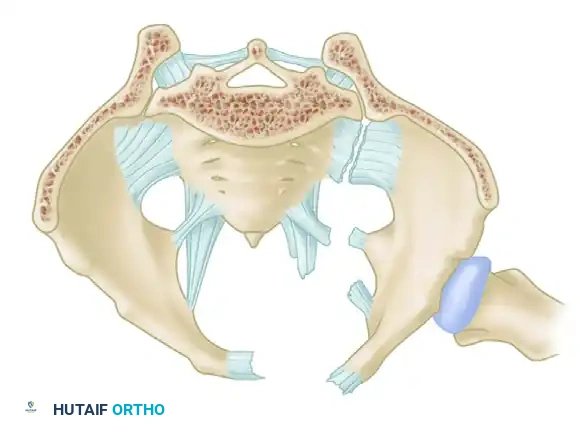

A profound understanding of pelvic osteoligamentous anatomy is the foundation of both classification and treatment. The pelvis is a ring structure composed anteriorly of the pubic and ischial rami connected at the symphysis pubis. A fibrocartilaginous disc separates the two pubic bodies, providing a degree of physiologic elasticity.

Posteriorly, the sacrum and the two innominate bones are joined at the sacroiliac (SI) joints. The SI joint itself possesses no inherent bony stability; its integrity relies entirely on a massive, complex ligamentous network.

The Posterior Tension Band

The posterior ligamentous complex is the primary weight-bearing and stabilizing structure of the pelvis. Tile famously compared the relationship of the posterior pelvic ligamentous and bony structures to a suspension bridge, with the sacrum suspended securely between the two posterior superior iliac spines.

The critical ligaments include:

* Interosseous Sacroiliac Ligaments: The strongest ligaments in the body, forming the primary restraint to vertical shear forces.

* Anterior and Posterior Sacroiliac Ligaments: Provide rotational stability to the SI joint.

* Sacrotuberous Ligaments: Resist rotation in the sagittal plane (flexion of the sacrum).

* Sacrospinous Ligaments: The primary restraints to external rotation of the hemipelvis.

* Iliolumbar Ligaments: Connect the L5 transverse process to the iliac crest, augmenting vertical and rotational stability.

Biomechanical Restraints

Pelvic stability is determined by these ligamentous structures acting across various planes. The primary restraints to external rotation (the "open book" deformity) are the ligaments of the symphysis, the sacrospinous ligament, and the anterior sacroiliac ligament. Vertical displacement of the hemipelvis is controlled by all the aforementioned structures. However, if the anterior structures are disrupted, vertical stability may still be maintained by intact interosseous sacroiliac, posterior sacroiliac, and iliolumbar ligaments.

Surgical Warning: A rotationally unstable hemipelvis may remain vertically stable due to an intact posterior tension band. Recognizing this distinction is paramount, as it dictates whether the patient requires simple anterior stabilization or complex posterior ring reconstruction.